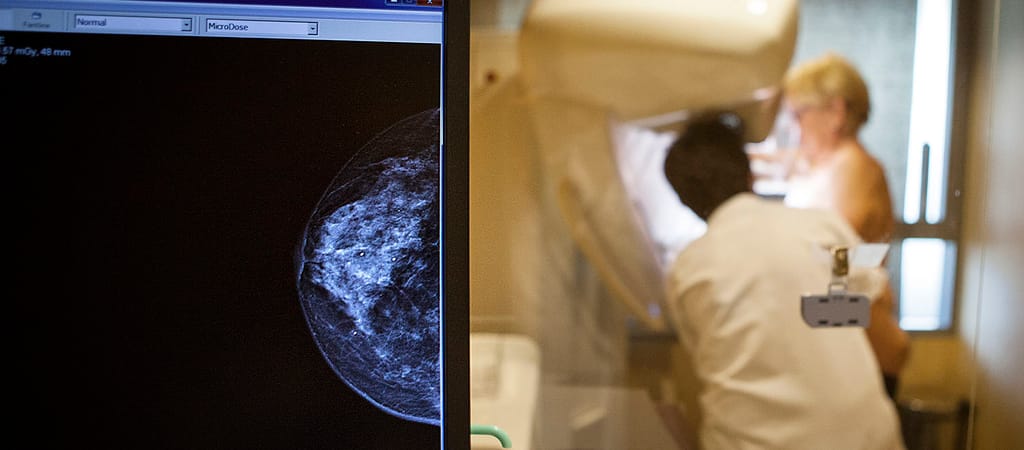

Emlőszűrés:

- csak a megkérdezettek 13,7 százaléka járt ilyen vizsgálaton 2022-ben,

- 15,9 százalék tavaly,

- 26,1 százalék ennél régebben,

- 44,3 százalék pedig bizonytalan vagy még soha, illetve neméből adódóan nem releváns számára ez a vizsgálat.